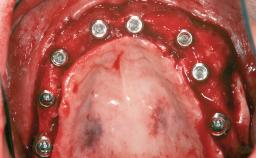

Shell Technique for Horizontal and Vertical Maxillary Bone Augmentation in a Partially Edentulous Patient with Aggressive Periodontal Disease

A 46-year-old woman was referred for treatment whose main complaints were mobility of her fixed partial dentures (right maxilla and left mandible) and periodontal bleeding during function. She also reported having taken systemic antibiotics to treat recurrent swelling in the area of the upper left molars. The patient had not seen a dentist for at least 2 years. She did not smoke and had no history of major systemic disease other than two minor orthopedic procedures some years back. The first-visit examination revealed poor plaque control, tooth mobility, periodontal disease, and a residual dentition widely associated with deep periodontal pockets.

Bone Augmentation Horizontal|Staged|Vertical

Augmentation Materials Autogenous chips|Autogenous block(s)|Xenogenous

Bone Volume Deficient vertically or deficient vertically AND horizontally